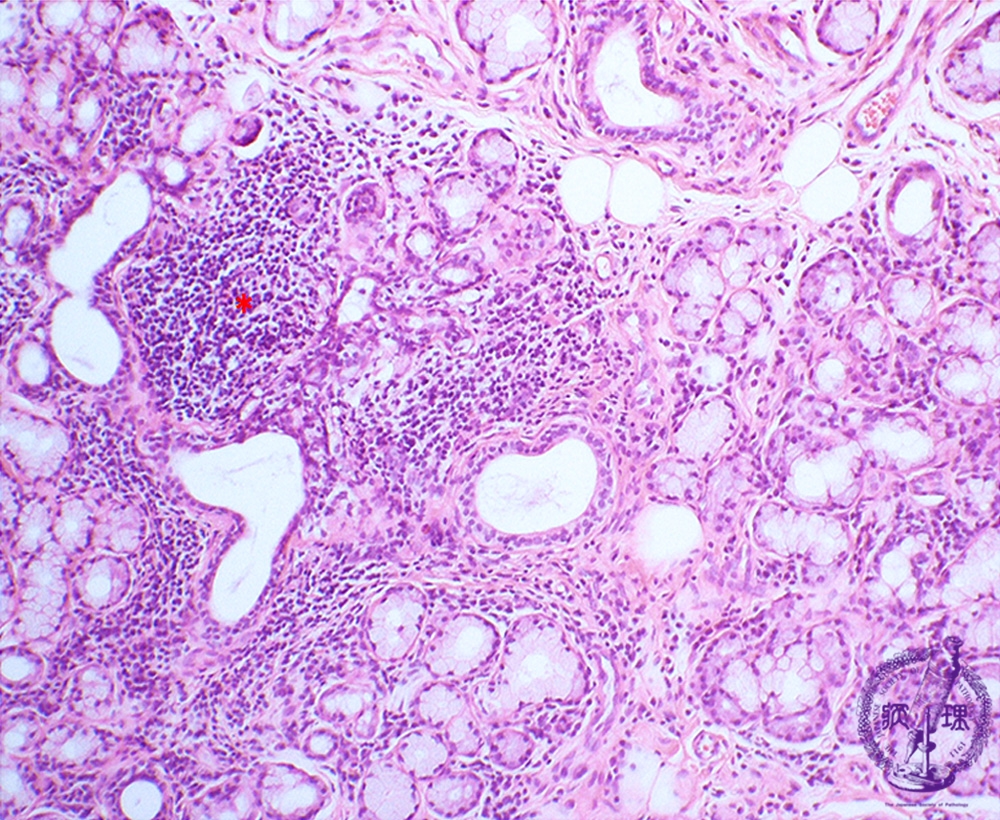

- 7.Oral, Salivary gland

- ★(4)Sjögren's syndrome

Microscopic finding (HE stain, low-power view):Labial gland biopsy. Lymphocytes (*), predominantly composed of T cells, focally infiltrate around interlobular ducts of minor salivary glands. In the background, there is acinar atrophy and destruction with (associated?) ductal dilatation.